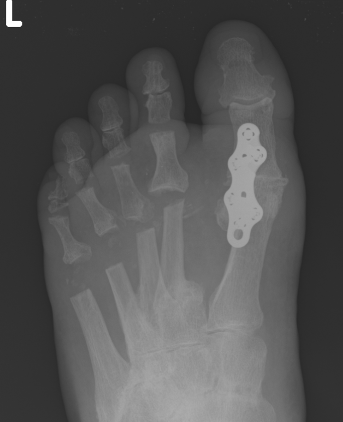

Operative Options

Synovectomy / Weil's osteotomy / Fowler's procedure (excision arthroplasty)

- Weil osteotomy in 72 RA feet

- 88% good or excellent results

- recurrent / persistent subluxation in 14%

Horita et al Foot Ankle Int 2018

- 16 resection arthroplasty v 18 Weil osteotomy in RA

- resection: outcome score 84, recurrence 3 feet

- osteotomy: outcome score 90, recurrence 1 foot